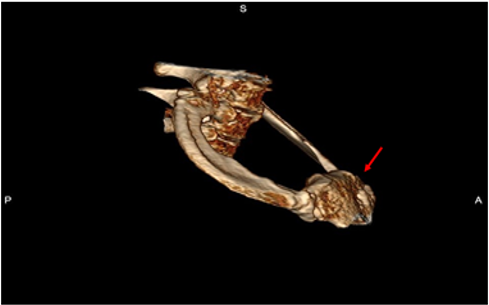

Preoperative MRA with maneuvers of the ipsilateral side in all patients (100%) in the N group revealed extrinsic compression of the subclavian vein at its junction with the innominate vein by a bony protuberance on the underside of the vein. (Figure. 1)

Figure 1: Preoperative MRA with maneuvers in a patient with Disputed Neurogenic TOS. The Arrows point to the extrinsic compression of the subclavian vein at its junction with the innominate vein by a bony protuberance on the underside of the vein.